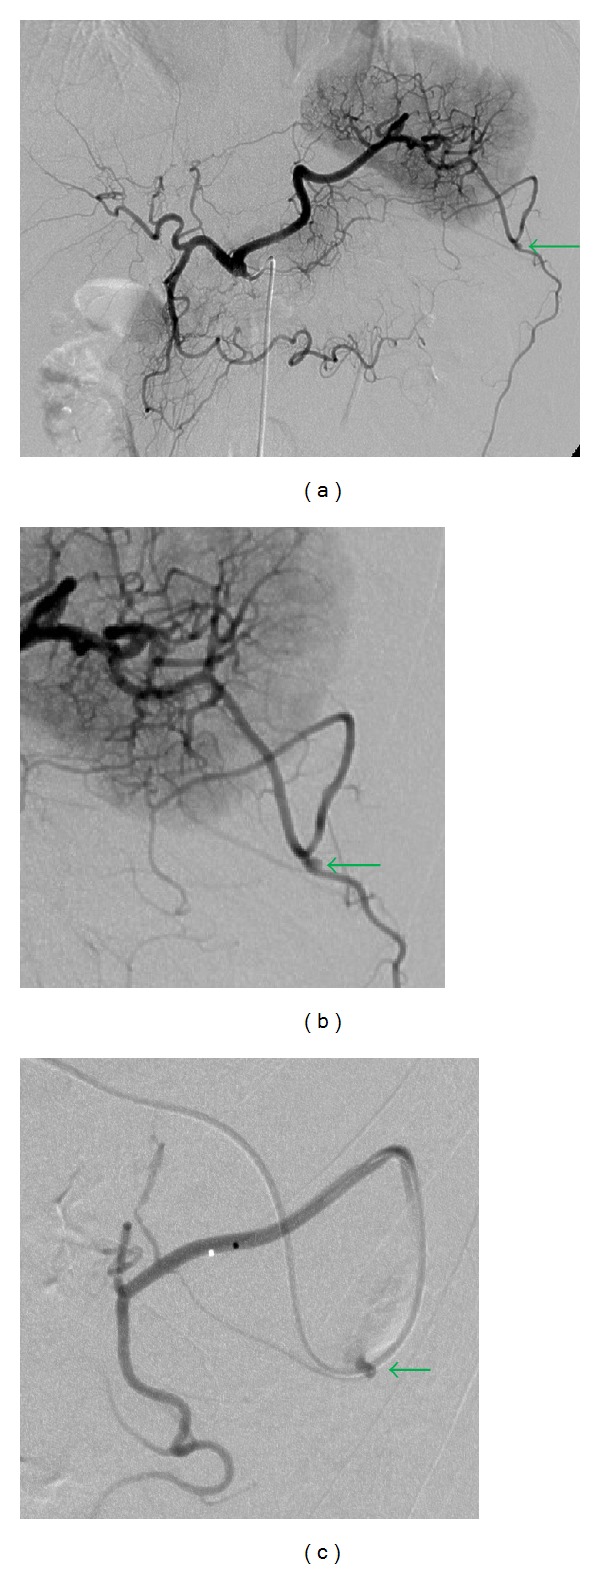

After the insertion of a 5-F sheath introducer from the right femoral artery under local anesthesia, a 5-F shepherd hook catheter (Terumo Clinical Supply, Tokyo, Japan) was advanced through the sheath introducer with its tip positioned in the celiac artery. Celiac arteriography revealed bleeding from the omental artery, which arose from the left gastroepiploic artery (Figure 2). The left gastroepiploic artery arose from the splenic artery. Superselective catheterization of the left gastroepiploic artery through the splenic artery was then performed with a 2.0-F microcatheter (Sniper 2-μ7; Terumo Clinical Supply, Tokyo, Japan), which was coaxially advanced through the 5-F catheter as distally as possible into the left gastroepiploic artery. Embolization with microcoils was performed. A 4 mm diameter, 6 cm long Interlock Fibered IDC Occlusion System (Boston Scientific, Natick, MA, USA) and a 2 × 4 mm Tornado Embolization Coil (Cook, Bloomington, IN, USA) were used as microcoils. After the embolization, the procedure was completed after confirming the disappearance of extravasation by angiography performed from the left gastroepiploic and celiac arteries (Figure 3).

Figure 2.

Celiac and left gastroepiploic arteriography revealed active extravasation (arrow) of the omental artery arising from the left gastroepiploic artery (a, b, c).